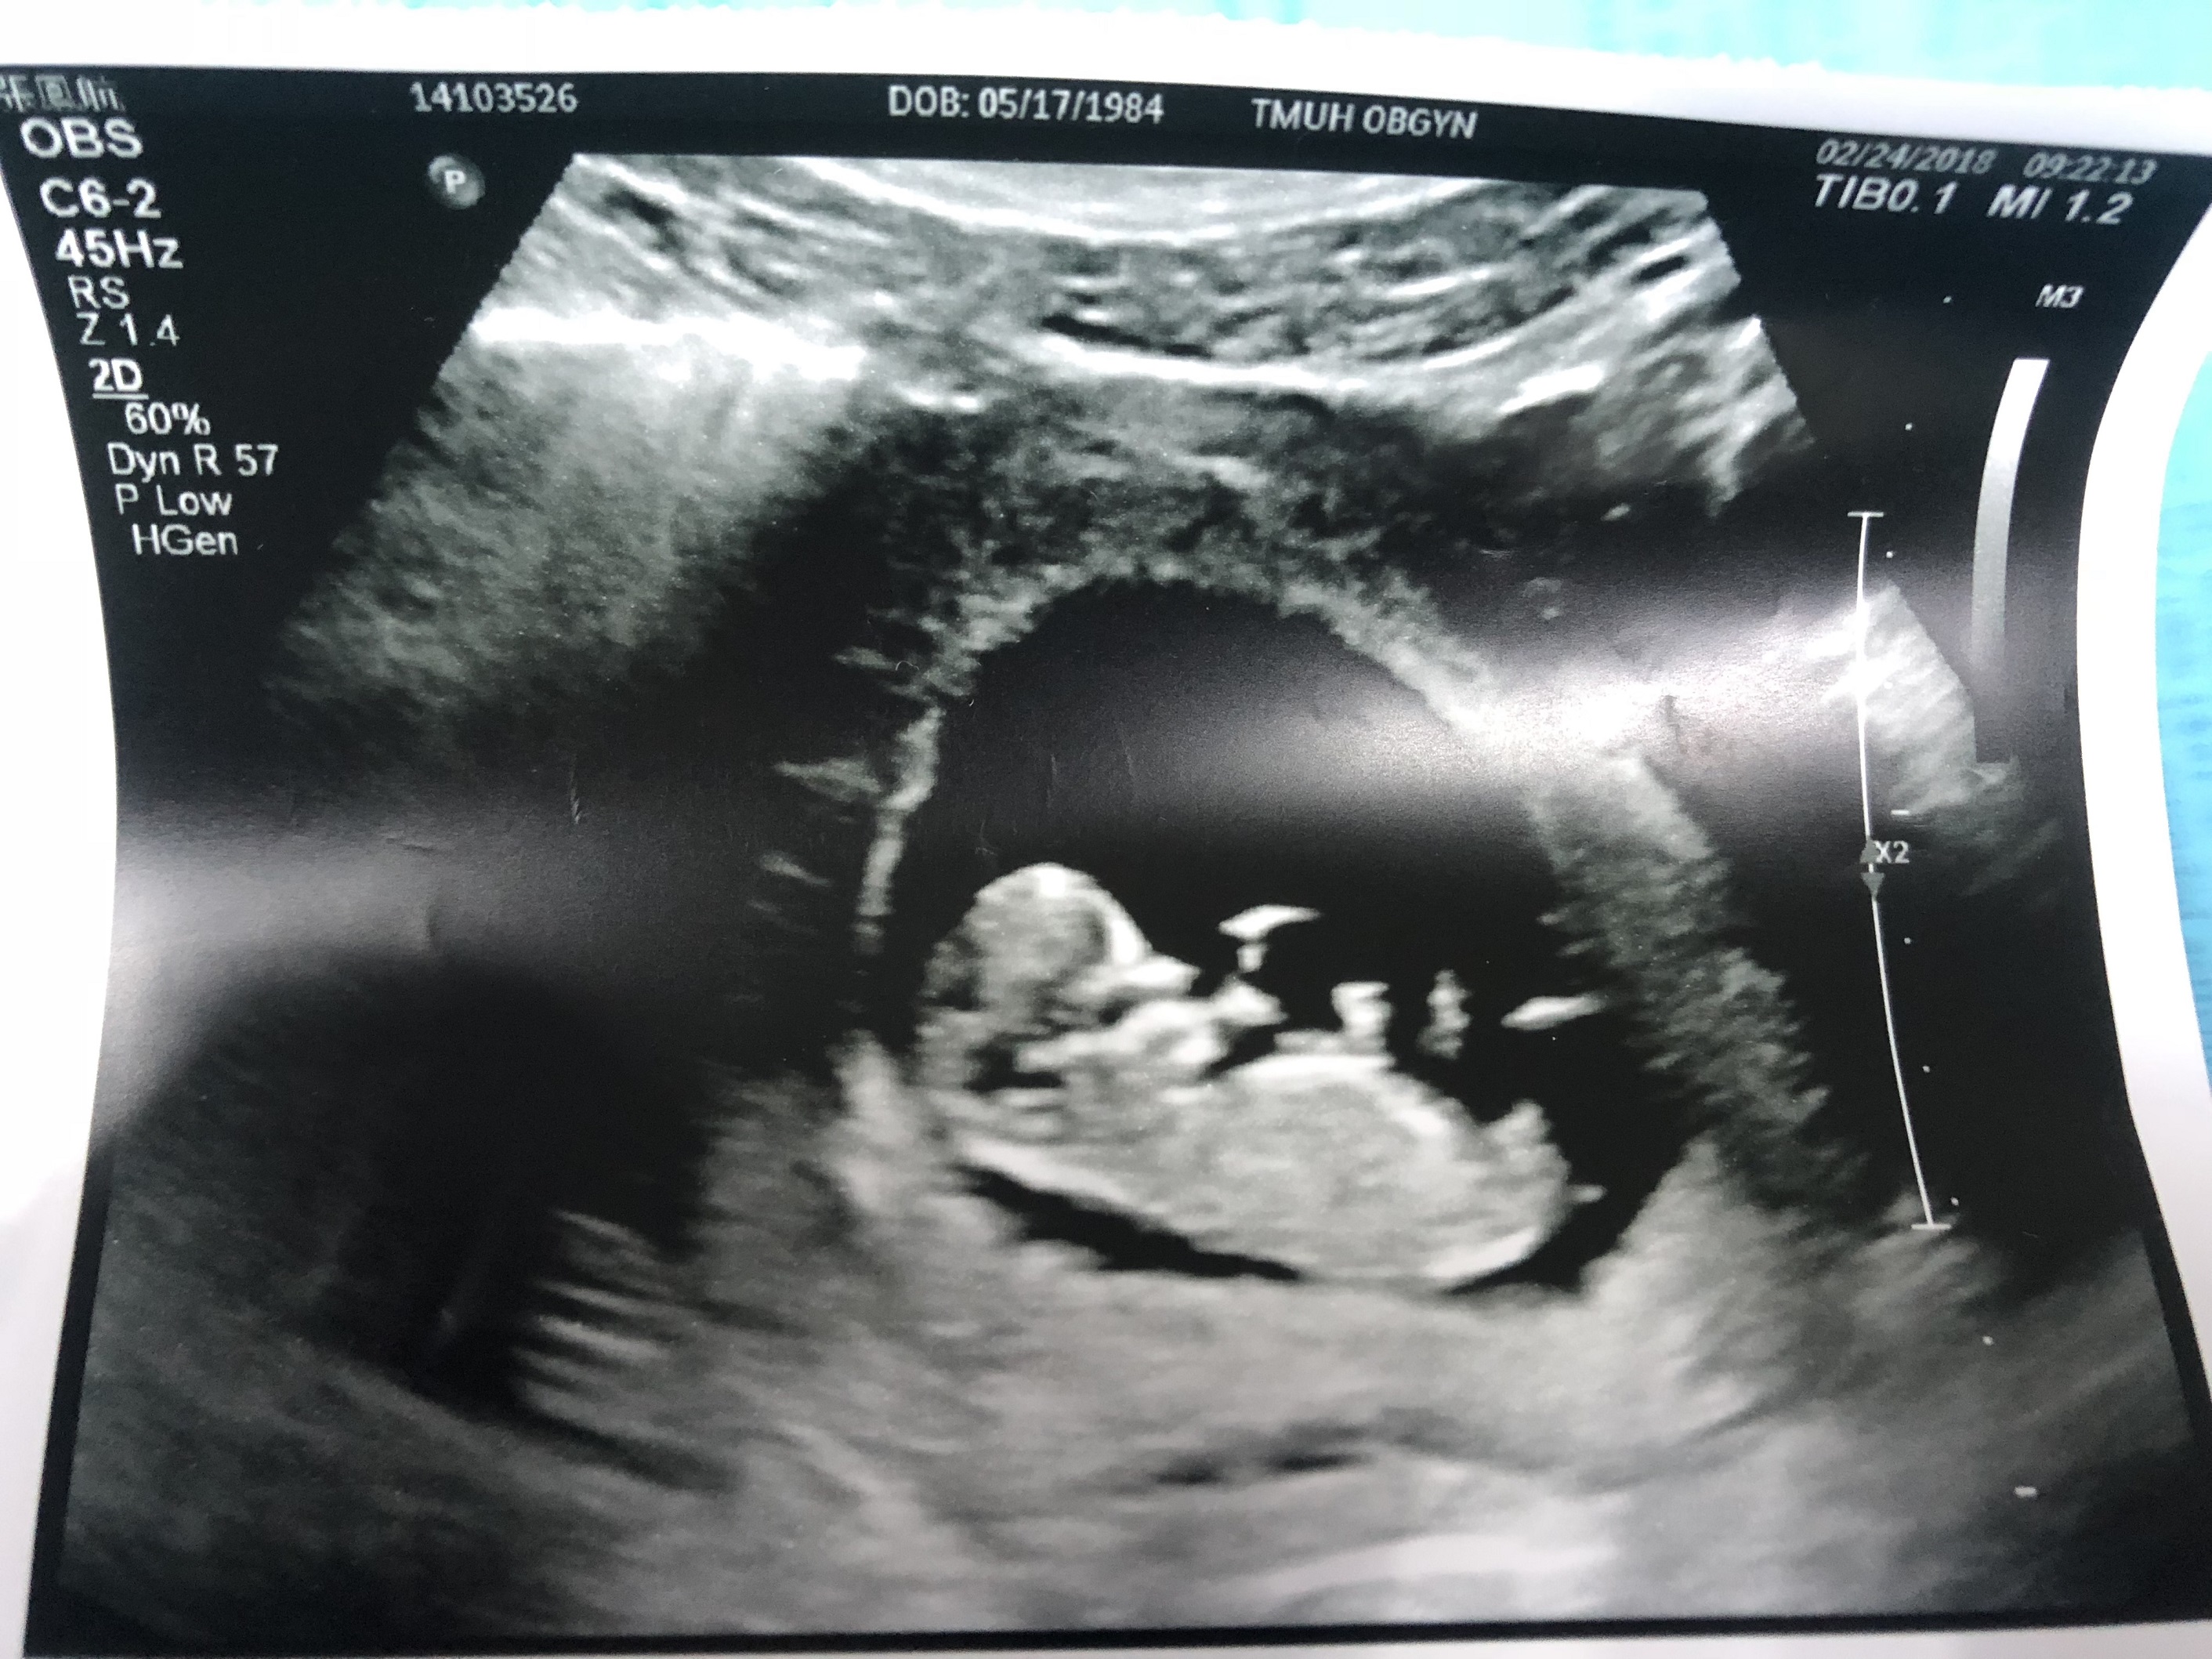

I'm obsessed with the whole gender guessing game!! I tried to do the Nub Theory but couldn't find the Nub of my baby. Can anyone help me with it? Is the baby boy or girl? Thank you all!!

That’s too early to guess. 12 weeks is the earliest, and even that isn’t as reliable as 13-14 weeks.

Boy